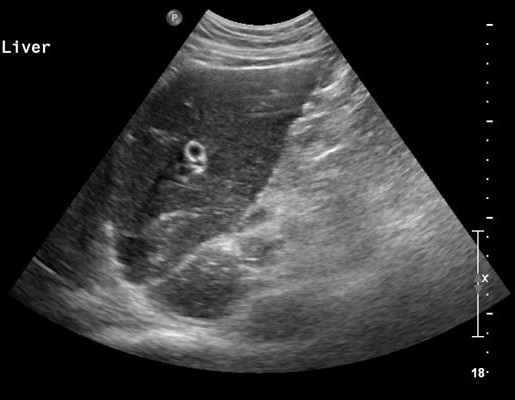

Echographie percutane

: Images echographiques du cholangite

infectueuse

aigue : Dilatation des voie biliaire intra et

extrahepatique , depasse 8mm avec voie

extrahepatique et 4mm des voies intrahepatique ,

Epaissisement de hypoattenuant de sa paroi . Image

de calcul canalicules et parfois de la

presence de pus intracanalaire .

Image

dilatation de voie biliaire intrahepatique.

Sa diametre de passe 6mm et image de calcul

vesiculaire se envoayait tres nette sur ce

coupe . Cholangite infectueuse |